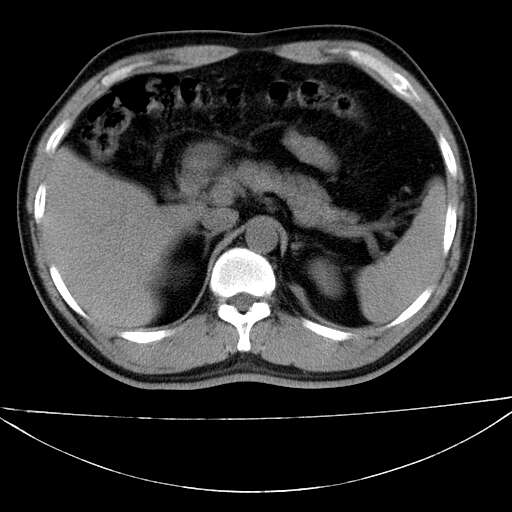

标题: CT21921:腹膜后腔肿物。患者男39Y。体检。增强扫描时间欠准 [打印本页]

标题: CT21921:腹膜后腔肿物。患者男39Y。体检。增强扫描时间欠准

左肋隔角占位,考虑胸膜间皮瘤

1)考虑左肺下叶后基底段(或左下胸后壁胸膜)软组织团块,性质待定;建议行进一步检查。2)左肾结石。

左膈肌角后腹膜腔见肿物影,其内见脂肪密度灶及软组织密度灶,强化不明显。病灶大部在后腹膜内。考虑异位嗜铬细胞瘤或脂肪肉瘤、畸胎瘤

1)考虑左肺下叶后基底段软组织团块,性质待定;建议行进一步检查。2)左肾结石。

左下肺隔离症,可见从胸主动脉发出异常血管供应